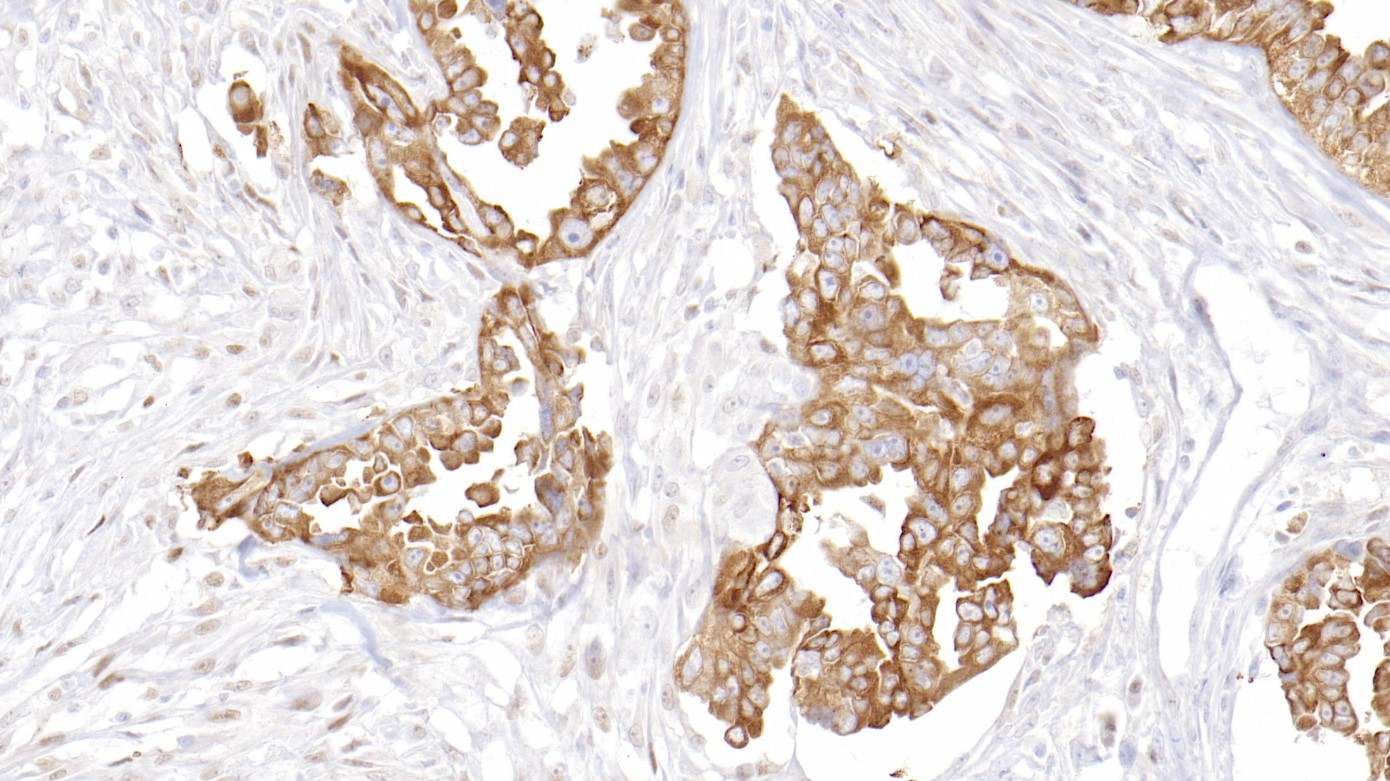

Topoisomerase II-α是一种核蛋白,分子量约为170 kDa,在DNA合成、RNA转录和有丝分裂的染色体分离中有重要作用。Topoisomerase II-α在S晚期、G2向M期转换过程及发育调节正常细胞中是一个敏感和特异性的标志物,而且在许多人肿瘤中是过表达的。Topoisomerase II-α表达减少是一些化疗药物受抵制的主要机制。

阳性对照

宫颈癌